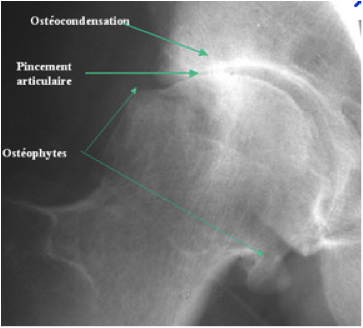

Dans la majorité des cas, une simple radiographie permet de faire le diagnostic de coxarthrose et d'en surveiller l'évolution. Votre chirurgien évaluera l'espace entre la tête fémorale et le cotyle : cet espace correspond à l'épaisseur du cartilage. Lorsque les os sont en contact (pincement articulaire), le cartilage est complètement usé.

Radiographie d'une hanche atteinte de coxarthrose

Arthrose de hanche (coxarthrose)